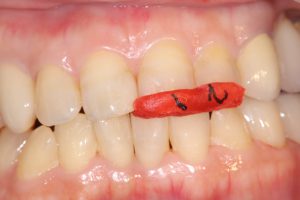

下の画像は噛み合わせ時の正面画像ですが、、

前歯の接触がない為、歯冠高径と前方基準となるジグを治療時には装着し確認しながら行われたそうです。基準をしっかり把握する『診断』を出来る医師はどのくらい存在するのでしょうか?私は、こんな治療を見るたび彼の治療に対する熱意と執念(笑っ)に敬服します